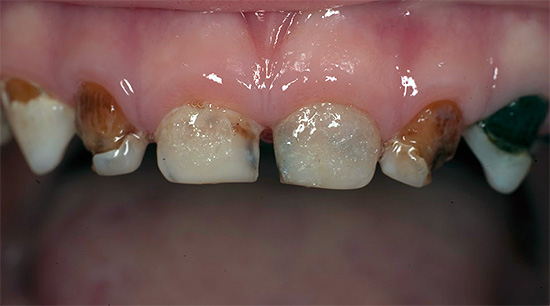

Oggi, a causa della popolarità della cura orale e della disponibilità di servizi dentali, la malattia è diventata meno comune, ma il problema è ancora rilevante nelle aree rurali e nei bambini in età scolare, quando quasi tutti i denti di un bambino sono affetti da carie (vedi l'esempio nella foto), e i genitori non sanno cosa fare in una situazione del genere.

Oltre al fatto che la carie è pericolosa per la salute, provoca dolore e limita la scelta del cibo, è anche un grave problema estetico. La foto sotto mostra un esempio di carie generalizzata:

Una malattia può portare allo sviluppo di complessi: una persona inizia a sorridere meno spesso, sente insicurezza e disagio costanti, smette di sentirsi attraente e si chiude. Ciò è particolarmente pericoloso se diventa la norma durante l'infanzia.